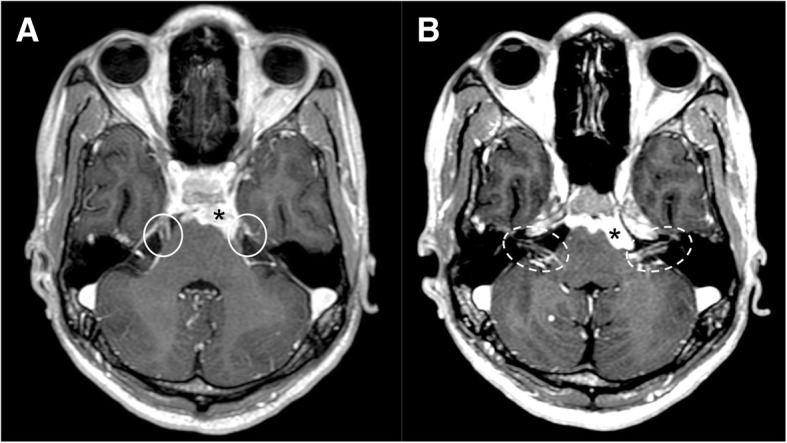

Fig. 14.

Hypoglossal schwannoma. MRI T2-weighted axial image (a), T1-weighted post-gadolinium axial (b), and coronal images (c) demonstrate an extra-axial expansive lesion (dotted circles), mildly hyperintense with heterogenous contrast enhancement, surrounded by cystic components. The mass is located along the course of the right hypoglossal nerve. CT (bone window, d) clearly shows the enlargement of the right hypoglossal canal (arrow). Atrophy of the right tongue muscles (asterisks) is well visible at CT (e) and T1-weighted axial sequence (f) as hypodense and hyperintense area, respectively